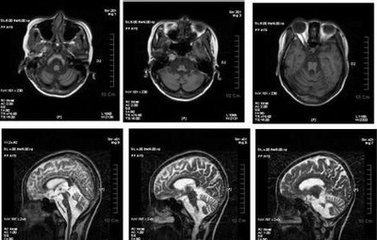

脑萎缩ct图片解说图

脑萎缩ct表现

脑萎缩图片

脑萎缩ct

脑萎缩图片对比

脑萎缩核磁

正常大脑和脑萎缩图片

脑萎缩ct图片

脑萎缩ct图片讲解

脑萎缩ct片子图片

脑萎缩ct图片解说